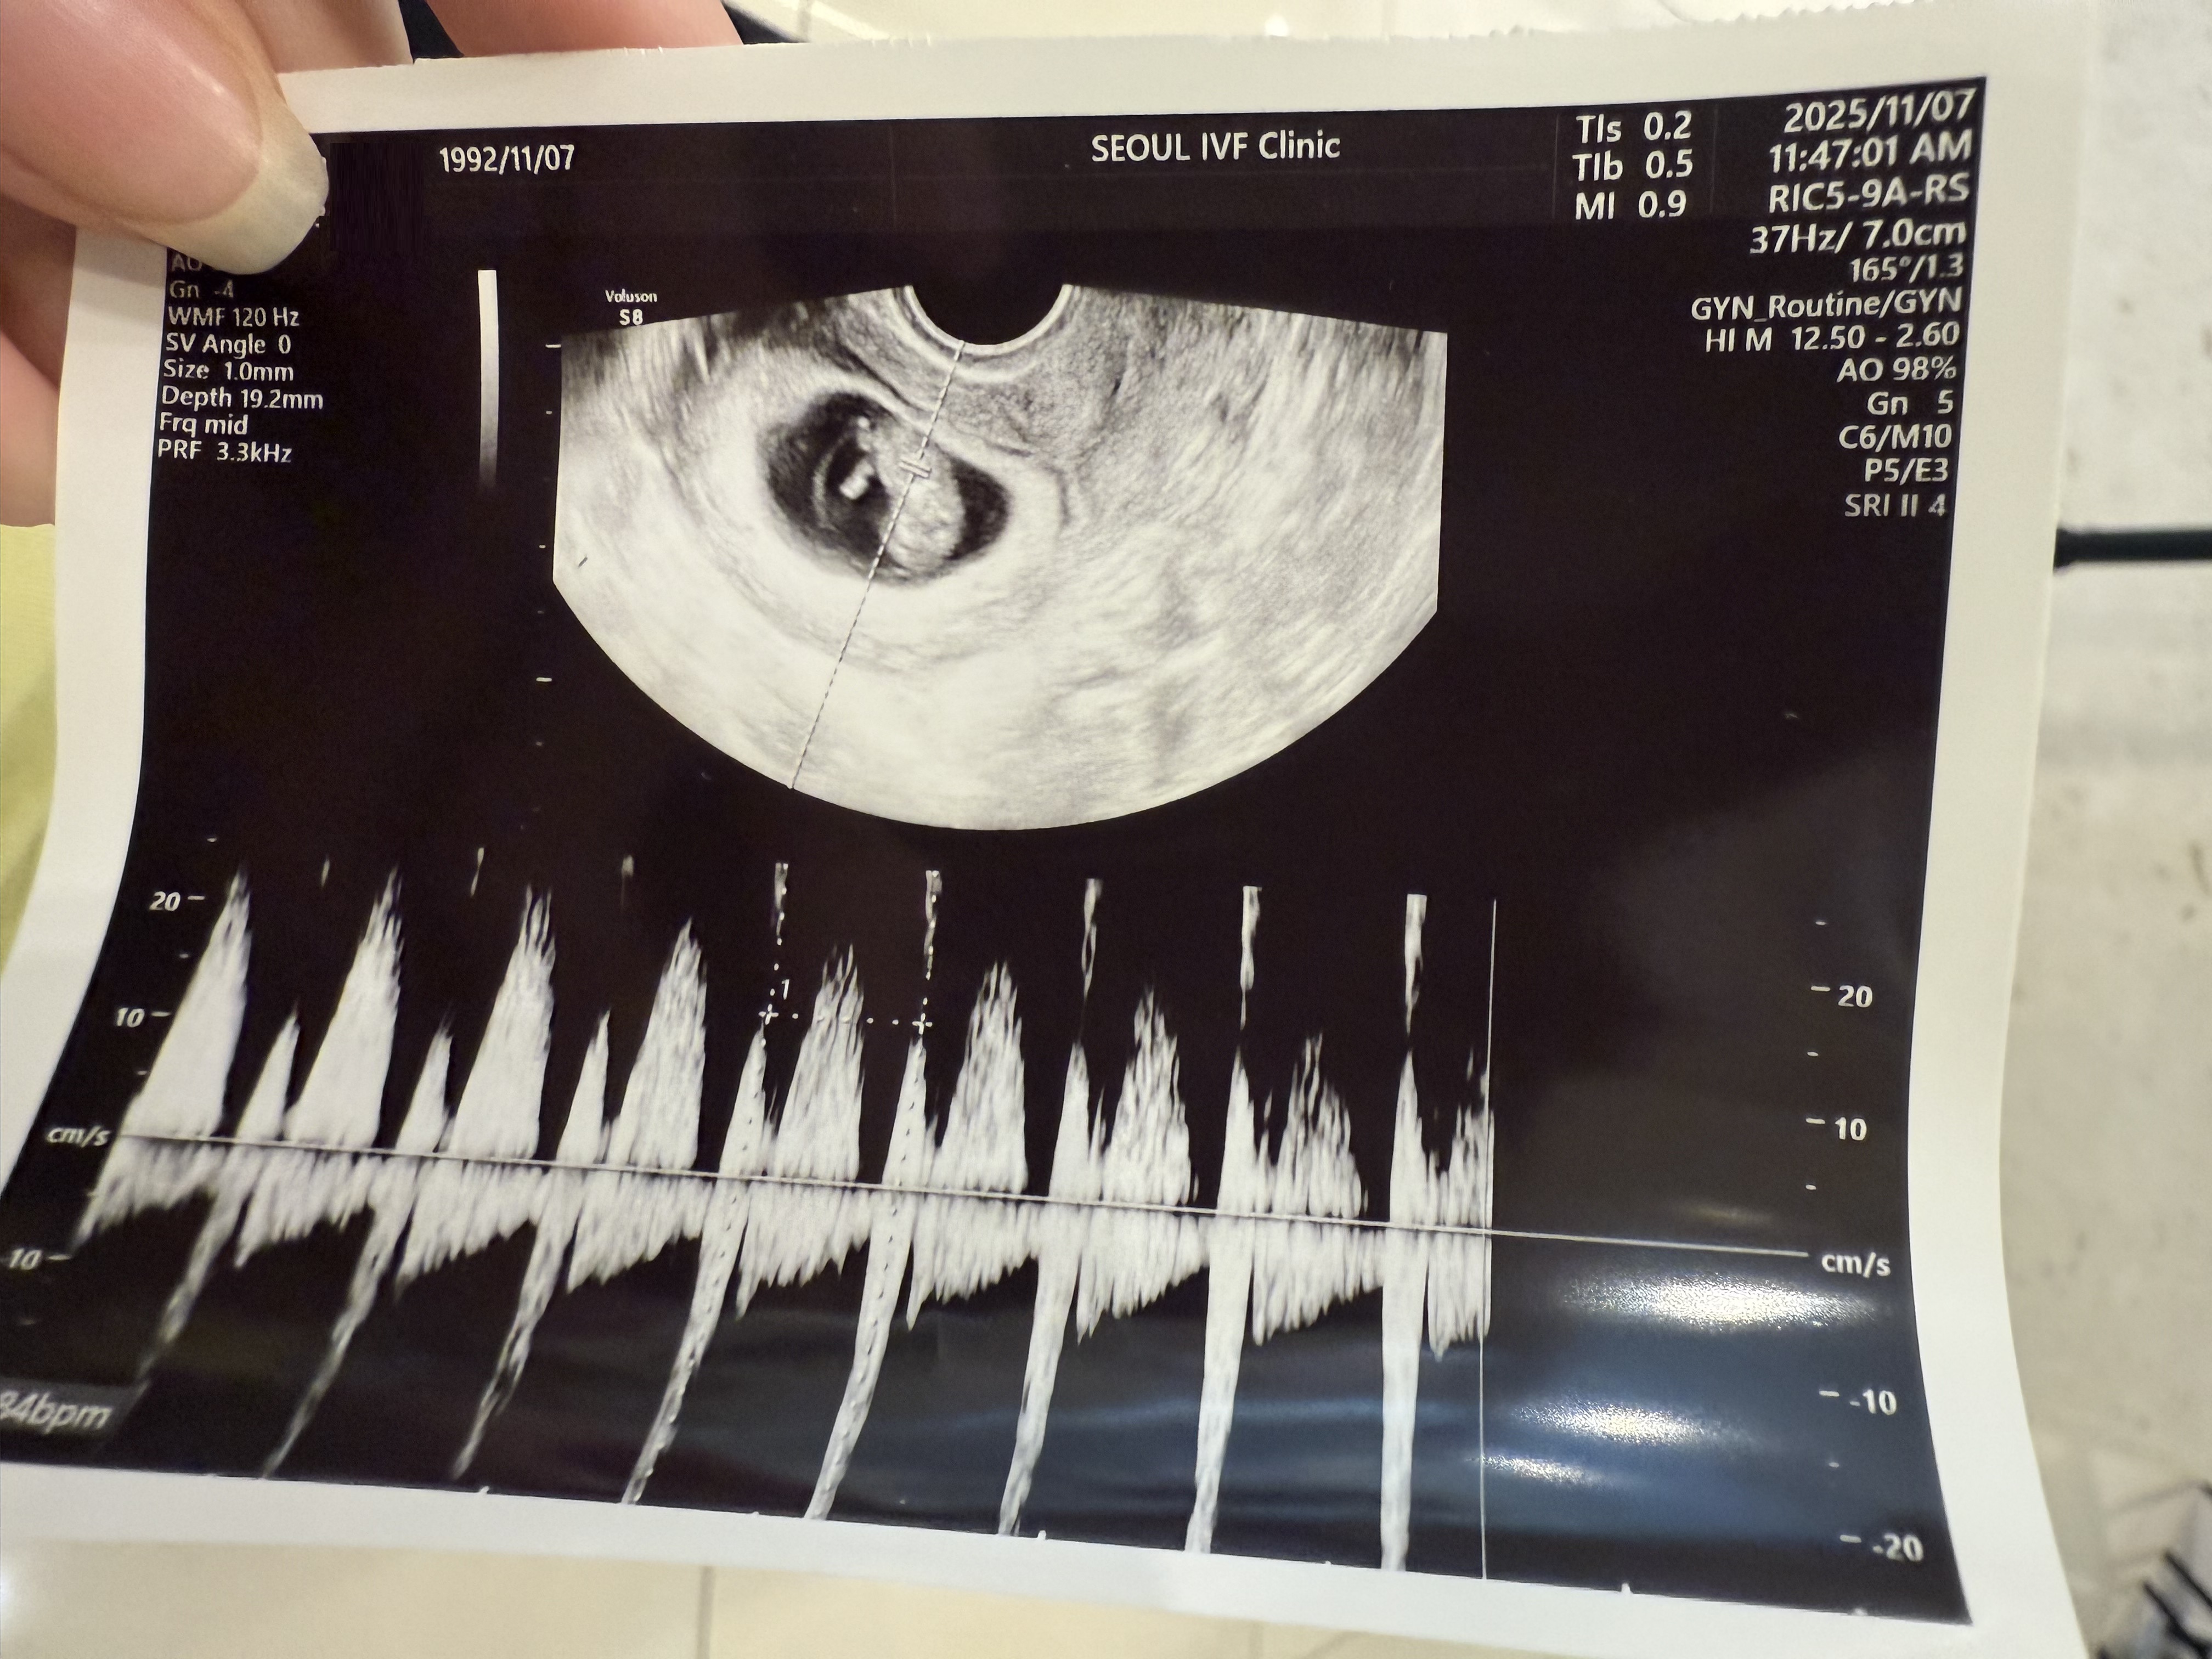

| 치료 도중 느꼈던 가장 기뻤던 순간과 절망적인 것들은 무엇인가요? 잊지 못할 경험이 있나요? | 가장 기뻤던 순간은 처음 아기 심장소리를 들었을 때였어요. 작고 빠르게 뛰는 심장 박동을 보는 순간, 모든 시간이 보상받는 느낌이었습니다. 가장 절망적이었던 순간은 하혈을 경험했을 때였습니다. 혹시 잘못된 건 아닐까 불안하고 무서웠지만, 다시 안정된 모습을 확인하며 한숨 돌릴 수 있었습니다. |